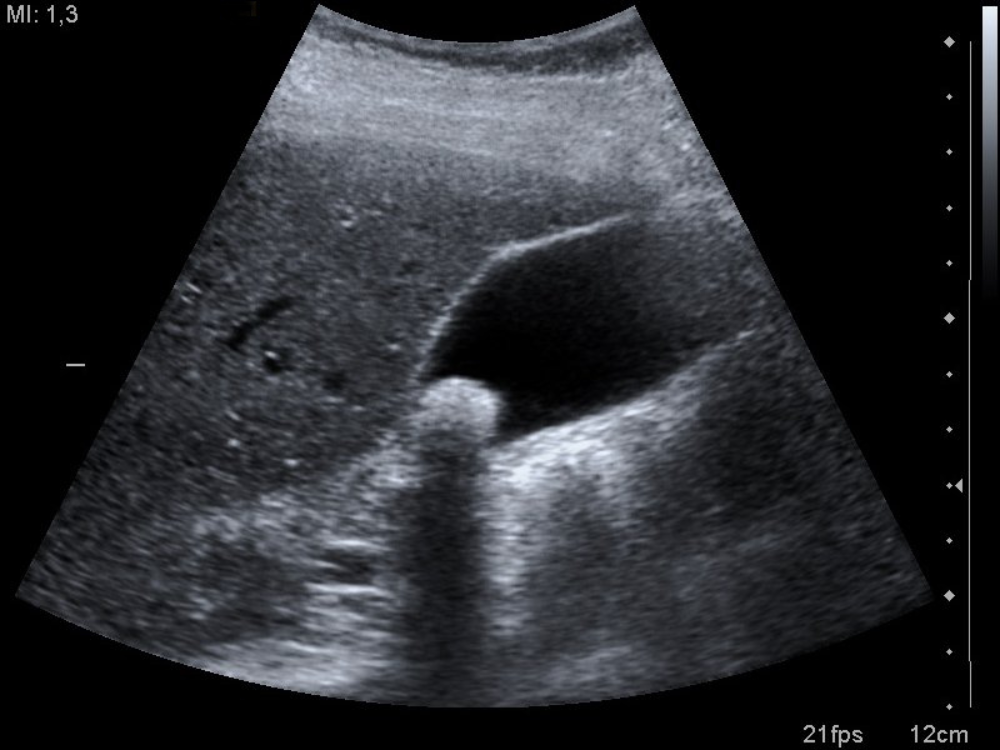

Ecografía de vesícula biliar con litiasis. Fuente: Wikimedia Commons

La exploración ecográfica del hipocondrio derecho evidencia la vesícula biliar con contenido líquido y una litiasis única, con los hallazgos característicos en ecografía: formación hiperecogénica con sombra acústica posterior.